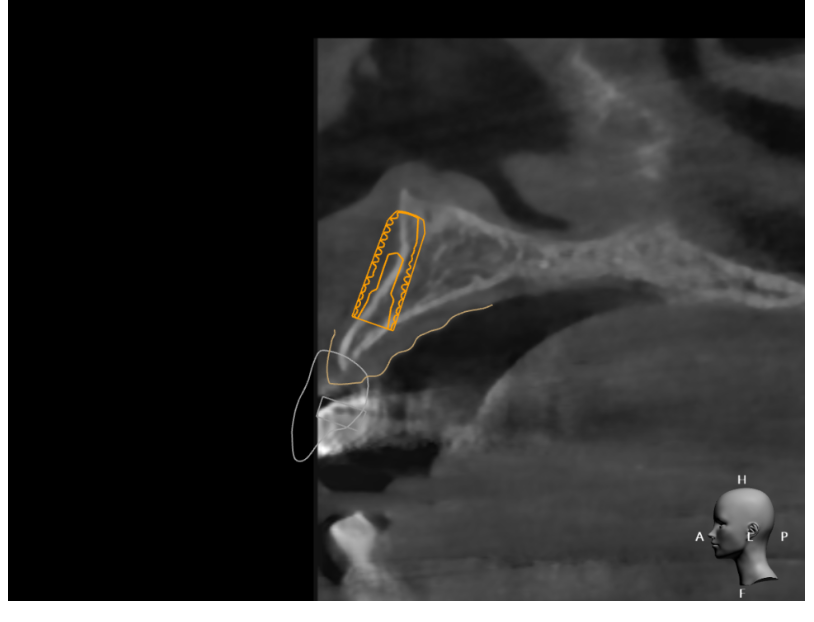

네비게이션 임플란트 수술 방식도 한몫 하죠

x-ray 만 찍어봐도 뼈 상태를 미리 정확하게 확인할 수 있고,

정밀한 각도와 위치로 식립이 가능해졌기 때문에

조건만 맞으면 발치 직후 바로 심는 것이 안정적인 치료법이 되었습니다.

그만큼 당일 식립은 정확한 진단과

고도의 기술력이 뒷받침 되어야 합니다.